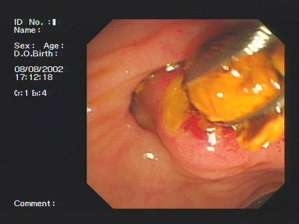

熊建光:适应症:胆总管结石、胆总管下端炎性狭窄、胆道蛔虫;胆肠吻合术后胆总管盲端综合征;急性梗阻性化脓性胆管炎;急性胆源性胰腺炎;壶腹部肿痛;Oddi括约肌功能障碍。